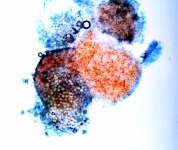

| Species Name: | Aspergillus spinulosporus |

| Taxonomy: | FUNGI Ascomycota, Eurotiomycetes, Eurotiales, Aspergillaceae |

| Characters: | CULTURE CONDITIONS heavy ascomata on PDA - // HUMAN/ ANIMAL PATHOGEN cerebral aspergillosis in a small bowel transplant patient - // MOLECULAR SYSTEMATICS calmodulin sequence has 99% identity to 5 strains of E. echinulata in the GenBank - fide P. Iwen (Click for publications citing UAMH 10948) |